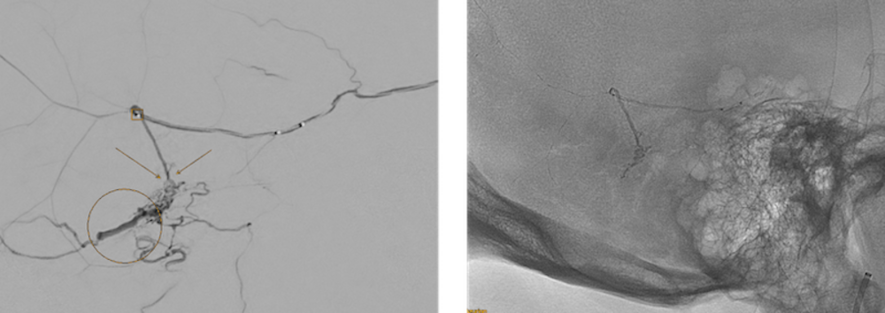

Vergleich Vorbefund (Bild links) mit Befund nach der Therapie (Bild rechts). Rechts zeigen sich die röntgendichten Embolisatanteile in der Fistel und der zuführenden Hirnhautarterie. Die Vene kontrastiert sich nicht mehr (nicht gezeigt). Die dAVF ist vollständig ausgeschaltet.